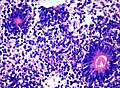

Rosettes

- Rosette = circular/flower-like arrangement of cells.[27]

- Perivascular pseudorosette = circular/flower-like arrangement of cells with blood vessel at the centre.[27]

- Homer-Wright rosette = (circular) rosette with a small (~100 micrometers ???) meshwork of fibers (neuropil) at the centre.[27]

- Medulloblastoma.

Homer-Wright rosettes (WC).